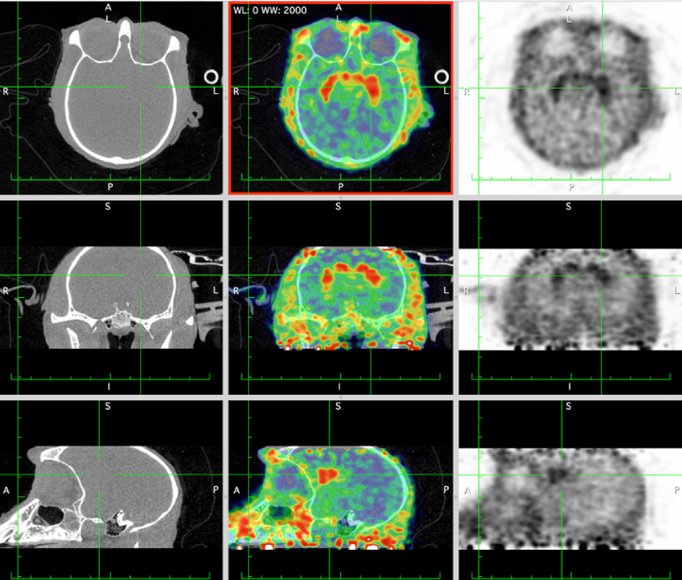

CASE 1: NHP PET/CT FDG brain imaging

• Courtesy of: University of Tours, Preclinical imaging department - PST ASB

Research objective: Investigation of FDG uptake in NHP brainĀ

Animal model: Female Macaca fascicularis, 4.5 kg

Acquisition protocol: PET imaging: 15 min per bed, 2 bed positions, 40 min after injection. CT imaging: 80kV, 52s per bed, 2 bed positions.

Processing and reconstruction protocol: PET: 3D OSEM, 0.84 mm isotropic voxel size. CT: 0.16 mm isotropic voxel size.

Biomarker or contrast agent: 18F-FDG; Injected activity: 85 MBq i.v.